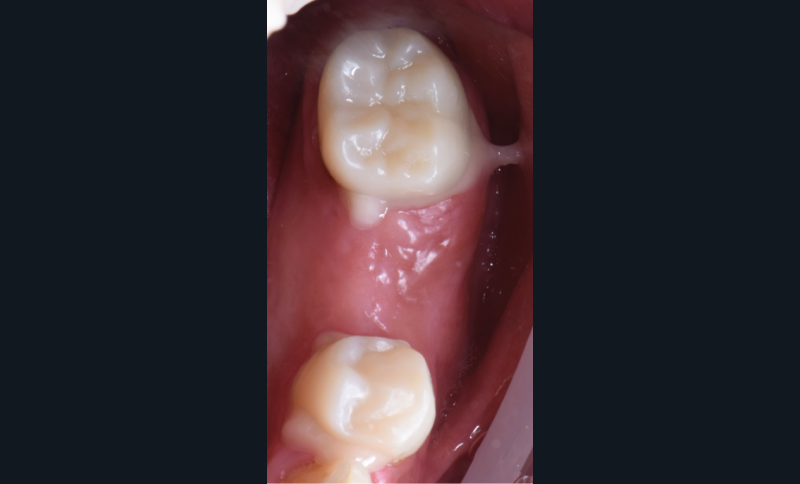

Au vu du contexte para-fonctionnel et de l’étendue de la perte tissulaire, des coiffes périphériques minimalement invasives ont été choisies afin de restaurer l’esthétique et la fonction. Actuellement, aucun consensus n’est fait sur le choix du matériau d’infrastructure à privilégier. Les matériaux hybrides usinables présentent des propriétés mécaniques, physiques et biologiques intéressantes en contexte d’usure sévère (e.g., module d’élasticité, résistance à la propagation de fêlures, facilité de réintervention). Une réhabilitation globale avec remontée de dimension verticale d’occlusion (DVO) par l’intermédiaire de coiffes composites renforcés en nano-céramiques est décrite.